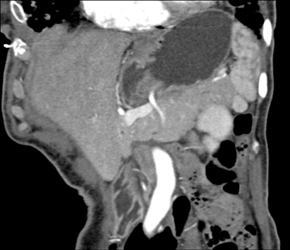

Diagnosis

Cystadenoma